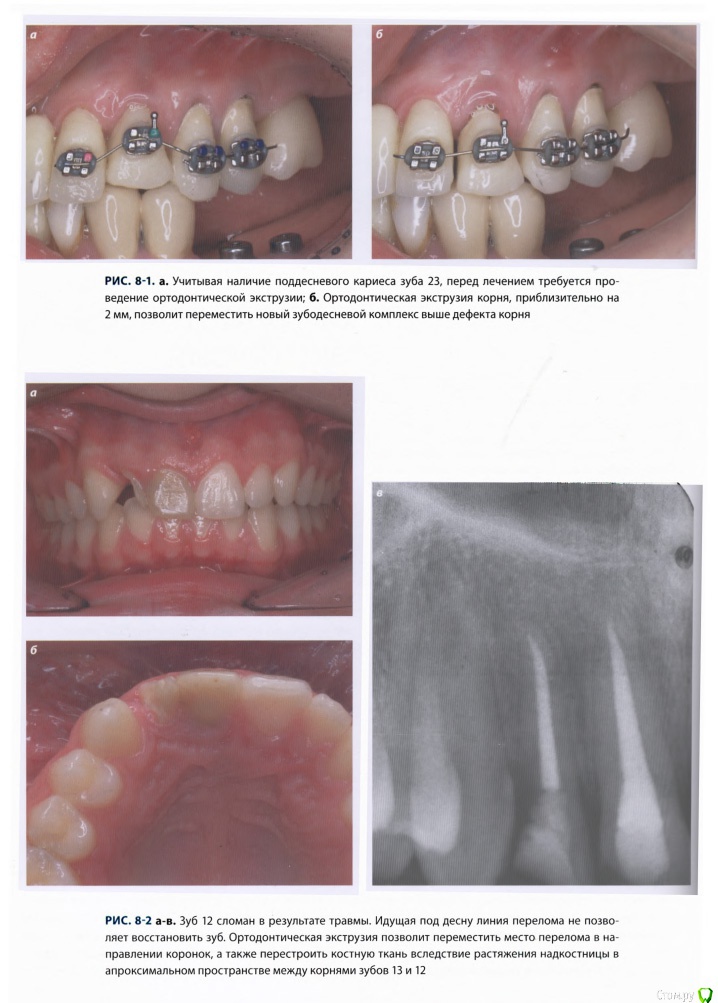

Romanson Опубликовано 25 июня, 2015 Поделиться Опубликовано 25 июня, 2015 Интересная тема, спасибо Колчанов за её создание. Вопрос такой - при ортоэкструзии обязательно нужно каждую неделю "подрезать" круговую связку? По теме есть вот такой кейс, автора к сожалению не помню. 2 Ссылка на комментарий

Romanson Опубликовано 25 июня, 2015 Поделиться Опубликовано 25 июня, 2015 И вот такой небольшой раздел из книжки 2011 года. Ссылка на комментарий